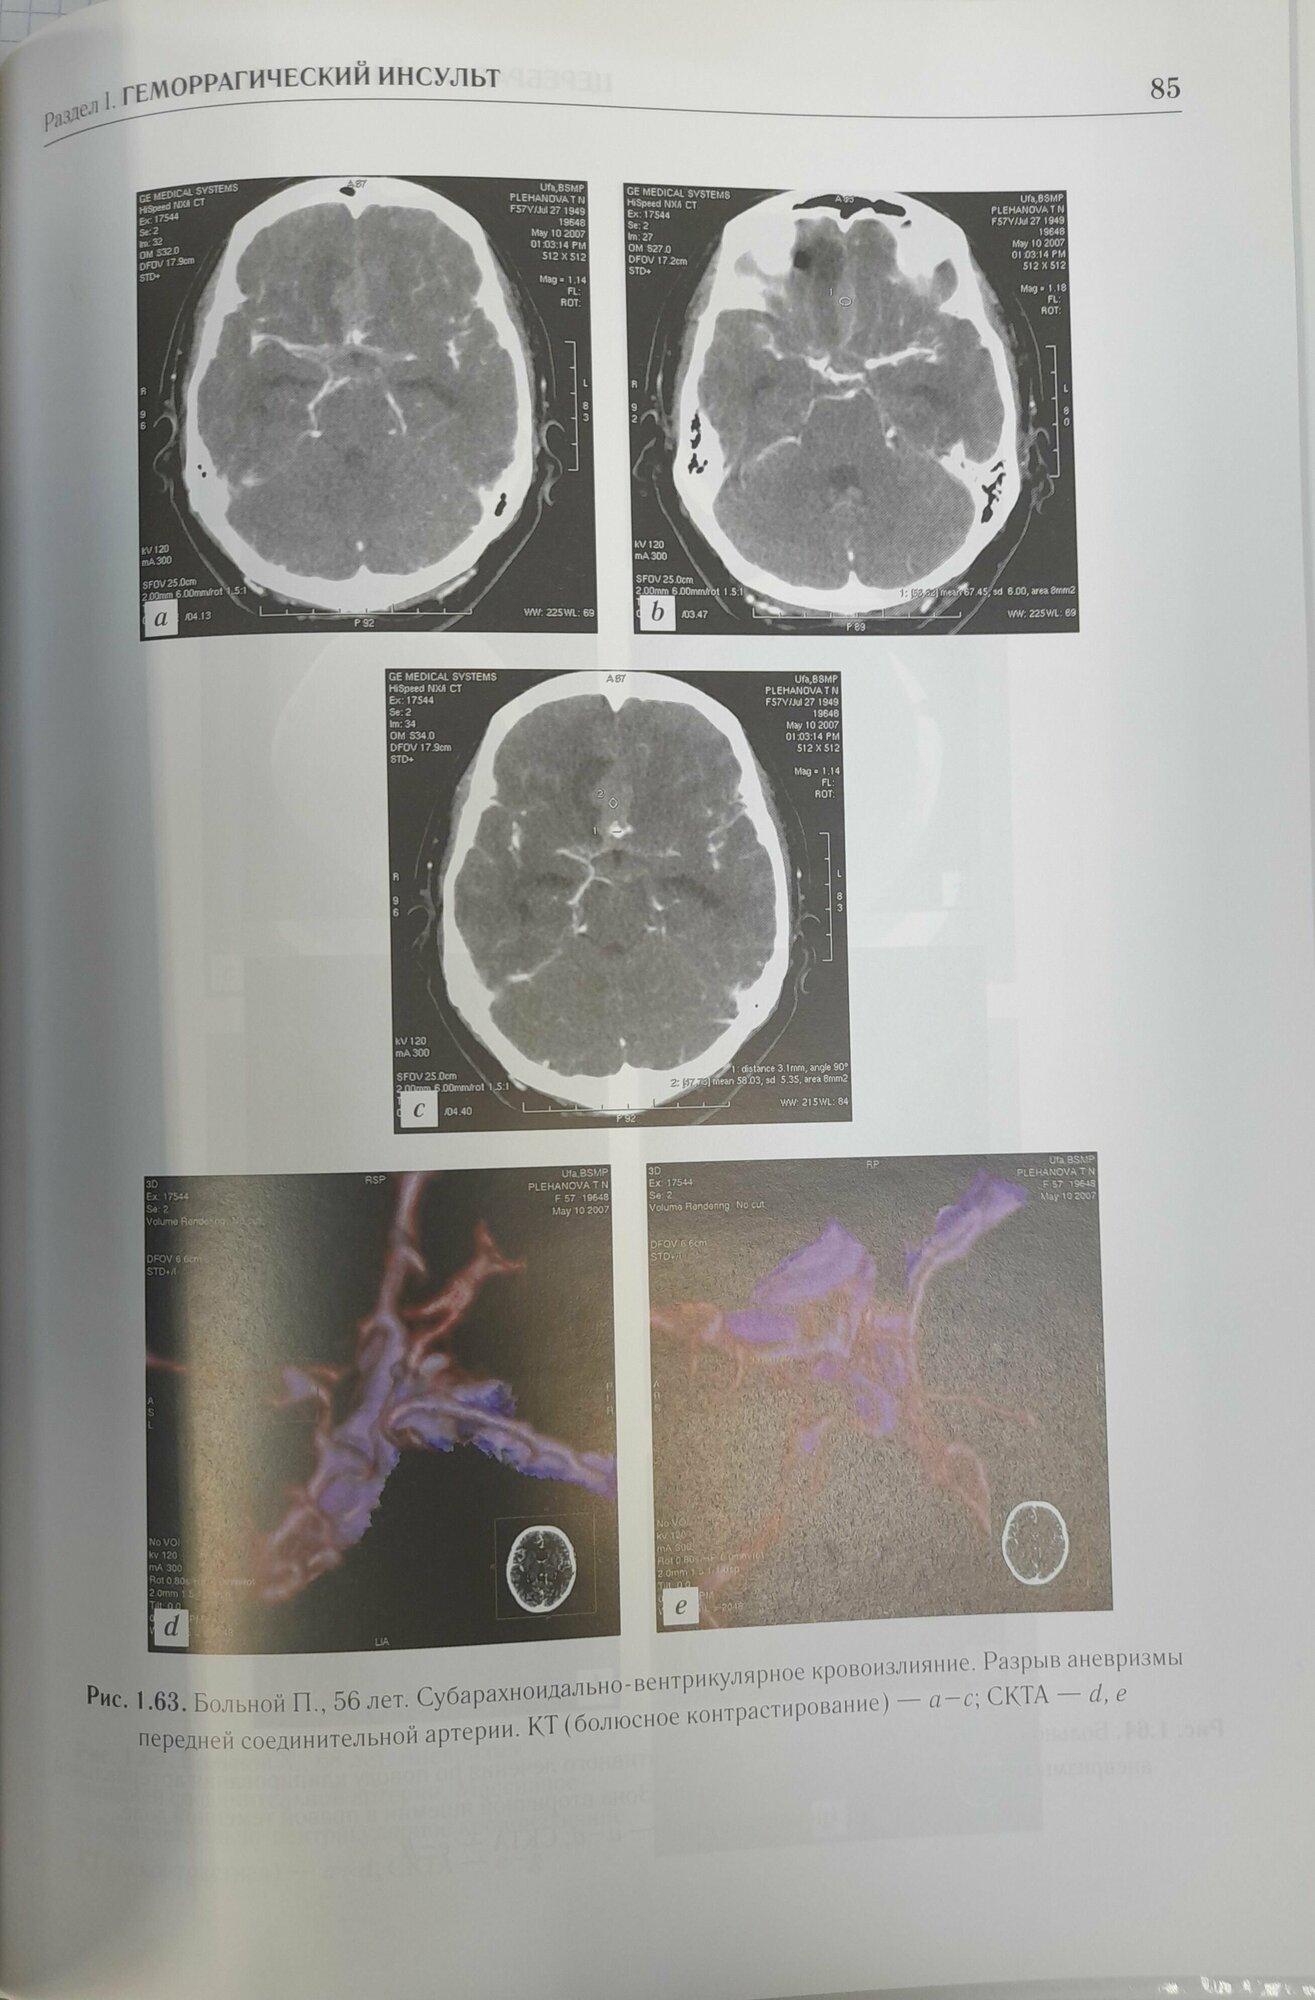

Церебральный инсульт. Атлас исследований (Новикова Лилия Бареевна, Скоромец Александр Анисимович, Сайфуллина Эльвира Идрисовна); ГЭОТАР-Медиа, 2012

Атлас посвящен актуальной проблеме современной ангионеврологии - изучению церебрального инсульта различными методами лучевой диагностики.

В книге описаны основные причины развития и симптомы острых нарушений мозгового кровообращения, алгоритмы диагностики, лечения больных с инсультом, изложены принципы дифференциального диагноза. Атлас позволяет четко представить картину церебрального инсульта в различных отделах головного мозга в зависимости от тактики и используемых технологий лечения. В нем наглядно приводится картина геморрагического инсульта в зависимости от этиологии, локализации, объема кровоизлияния, а также лучевой контроль при оперативном методе лечения. Детально изложена клиника острого ишемического инсульта в зависимости от его подтипа и характера локализации процесса, показана динамика ишемического поражения мозга на различных стадиях заболевания при медикаментозной терапии. Авторы надеются, что атлас будет полезен врачам лучевой диагностики, неврологам, нейрохирургам, а также интернам, ординаторам и врачам, получающим постдипломное образование по вышеперечисленным специальностям.